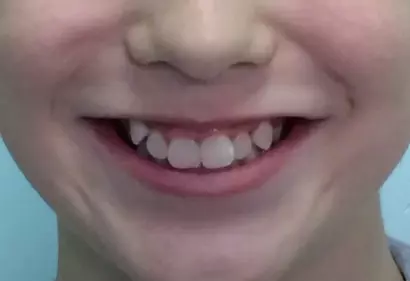

- Брекеты

- Эстетика